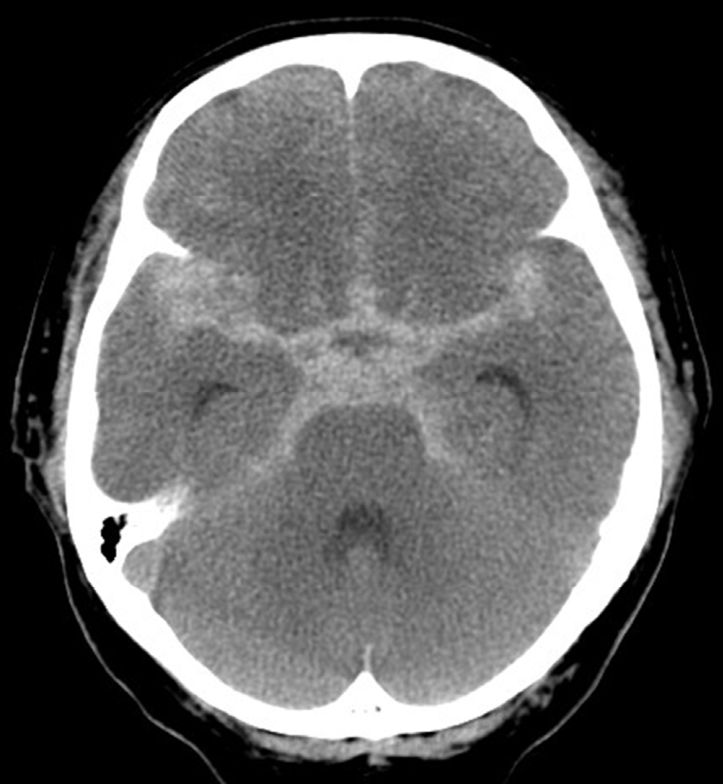

To address these gaps, we introduce KorMedMCQA-V, a Korean medical licensing examination-style multimodal multiple-choice question answering benchmark. KorMedMCQA-V contains 1,534 questions with images from Korean licensing exams, with roughly 70% having a single image and 30% having multiple images, reflecting common multi-panel exam formats. For example, Figure 1 shows a representative item requiring diagnosis from a brain CT. We evaluate VLMs spanning general-purpose, medical-specialized, and Korean-specialized families under a unified zero-shot protocol, analyzing performance by image modality, model type, and single- vs. multi-image settings.

Refer to caption Question: 67세 남자가 6시간 전부터 갑자기 머리가 깨질 듯이 아파서 응급실에 왔다. 뒷목이 당기고, 멍한 느낌이 들었고, 어지럽고 메스꺼워서 토했다. 혈압강하제를 복용 중이다. 혈압 183/84 mmHg, 맥박 51회/분, 호흡 18회/분, 체온 36.5C이다. 의식은 명료하다. 뇌 컴퓨터단층촬영 사진이다. 진단은? (A 67-year-old man presents to the emergency room with a 6-hour history of sudden-onset severe headache. He reports neck stiffness, mental fogginess, dizziness, and vomiting. He is on antihypertensive medication. Vital signs: BP 183/84 mmHg, pulse 51/min, RR 18/min, temperature 36.5C. He is alert. Brain CT is shown. What is the diagnosis?) A. 뇌내혈종 (Intracerebral hematoma) B. 경막외혈종 (Epidural hematoma) C. 경막밑혈종 (Subdural hematoma) D. 뇌실내출혈 (Intraventricular hemorrhage) E. 거미막밑출혈 (Subarachnoid hemorrhage)

Figure 1: Representative KorMedMCQA-V multiple-choice item with an associated medical image (imaging modality: CT). English translations are provided in parenthesized italics for readability. Models are given the full question stem, all answer choices, and the image(s), and must output a single option label (A–E).